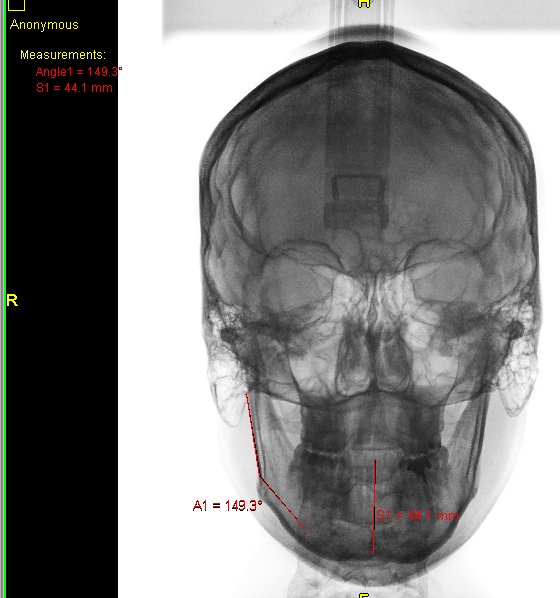

Algunos ejemplos de imágenes digitales

Pulse en las imágenes para ver la ampliación

Se agregó en rojo una medición hecha con la herramienta de medida